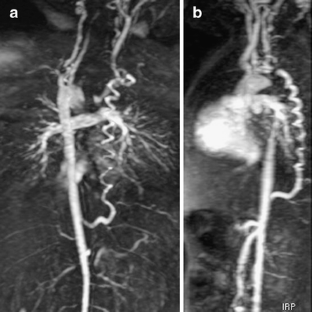

An isolated left subclavian artery is a rare anomaly. We report a 9-month-old boy with an isolated left subclavian artery associated with tetralogy of Fallot and the right aortic arch. MRI and angiography show that the blood supply through the left subclavian artery was maintained by a large tortuous collateral artery from the abdominal aorta. This type of collateral artery structure is unique.

Fig. 2